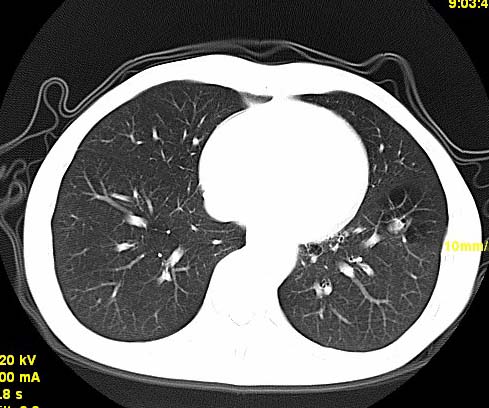

以下是引用wangzhengyuan在2007-11-11 23:31:00的发言:[br]钙化灶,看上去不像转移。

以下是引用zjzjr在2007-11-12 8:35:00的发言:[br]考虑错构瘤,建议定期复查.

以下是引用卜一在2007-11-12 5:59:00的发言:[br]病灶本身不像转移,不知有没有以前的胸部ct片,若有,则可以对比以下,若是新出现病灶,应高度警惕“转移”的可能![br]